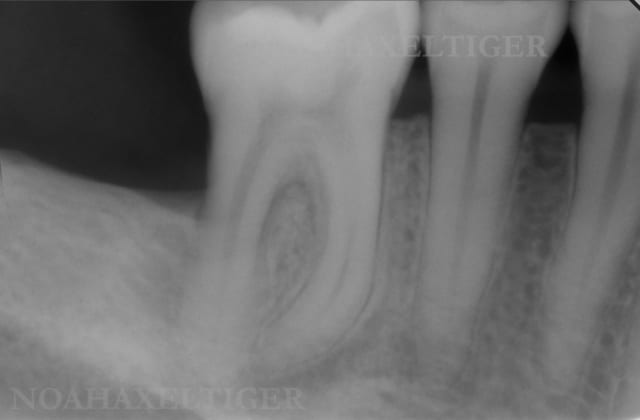

Je te montre quelques cas cliniques traités avec Emdogain et sans matériaux de comblement sur lesquels j'ai plusieurs années de recul :

Cas 1

Initial 46 th2se3 - Eugenol

Final 46 s2gxlk - Eugenol